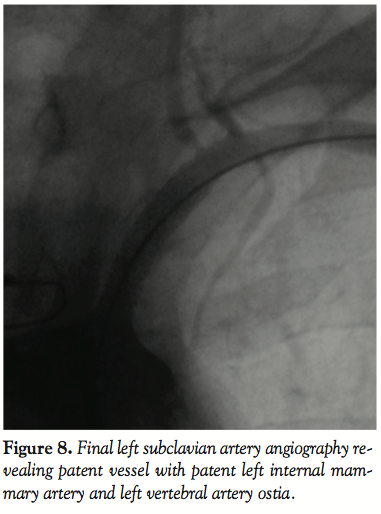

Post-procedural  angiography demonstrated a widely patent stent with anterograde flow within the LIMA up to the anastomosis and within the left VA (Figure 8). The distal end of the stent was located at the origin of both the left vertebral and LIMA. After the procedure, the left radial pulse became palpable and was   noticeably strong and equal in volume to the right one. The blood pressure difference between the upper limbs disappeared. Three months later, the patient was asymptomatic and there was no upper limb pressure difference.